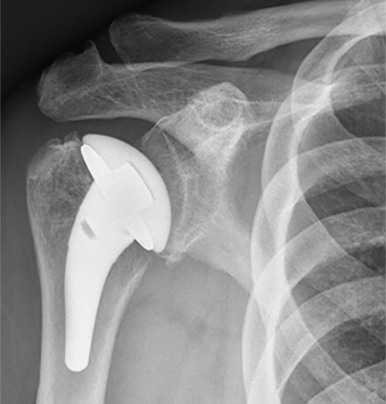

Anatomic Right Shoulder Arthroplasty

Jeff is a 63 year old male who presented with years of sharp, incapacitating right shoulder pain. After a course of nonoperative treatment he underwent an anatomic right shoulder arthroplasty. He has done a great job in PT postoperatively and is back to golfing and sleeping soundly again!